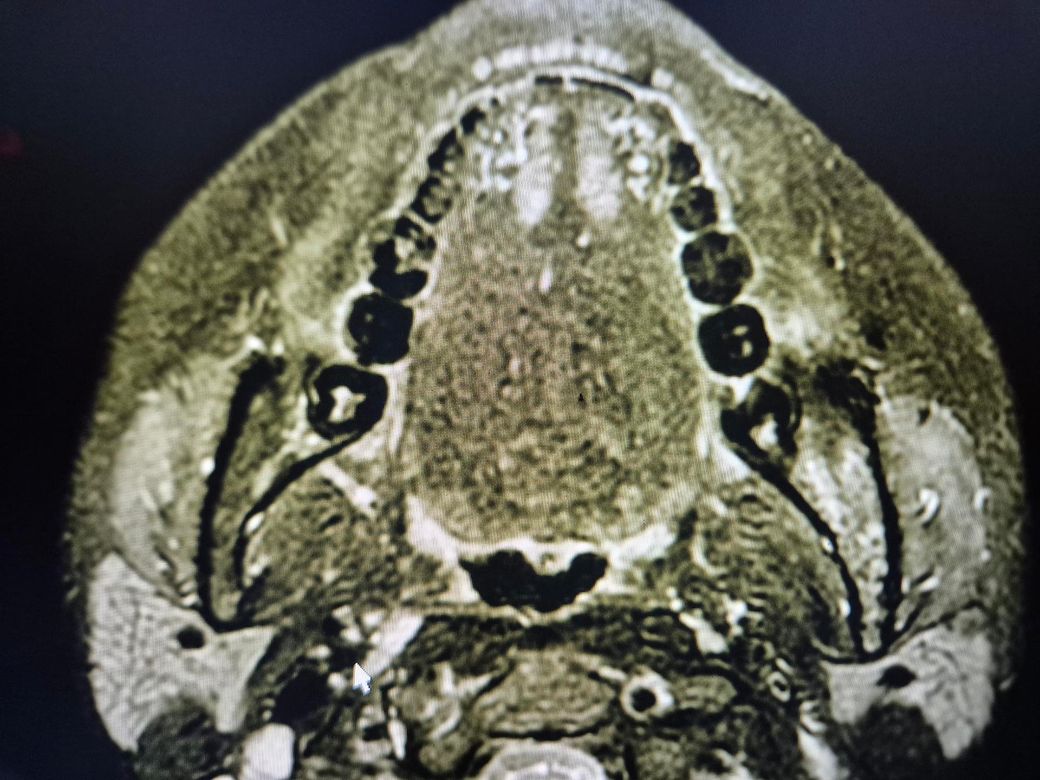

좌측 턱에 뭔가 있어서 질문드립니다.

치과에서 사랑니 빼다가 발견 한건데 저게 뭘까요?

뭔가 딱딱해 보인다고 들었던거 같은데, 콧구멍 쪽에도 있는거 같다는데 골종양 이런건가요?

• 2번 째 사진

엑스레이 상으로 크게 문제가 있어 보이는건 없습니다. 그냥 경화가 된부분이 보이는거 같습니다.

골육종 등 악성종양의 양상은 아닌 것으로 보입니다. 엑스레이 양상으론 fibrous dysplasia의 가능성이 있어보이나 정확한 진단은 대학병원 영상의학과 가보셔야 합니다.